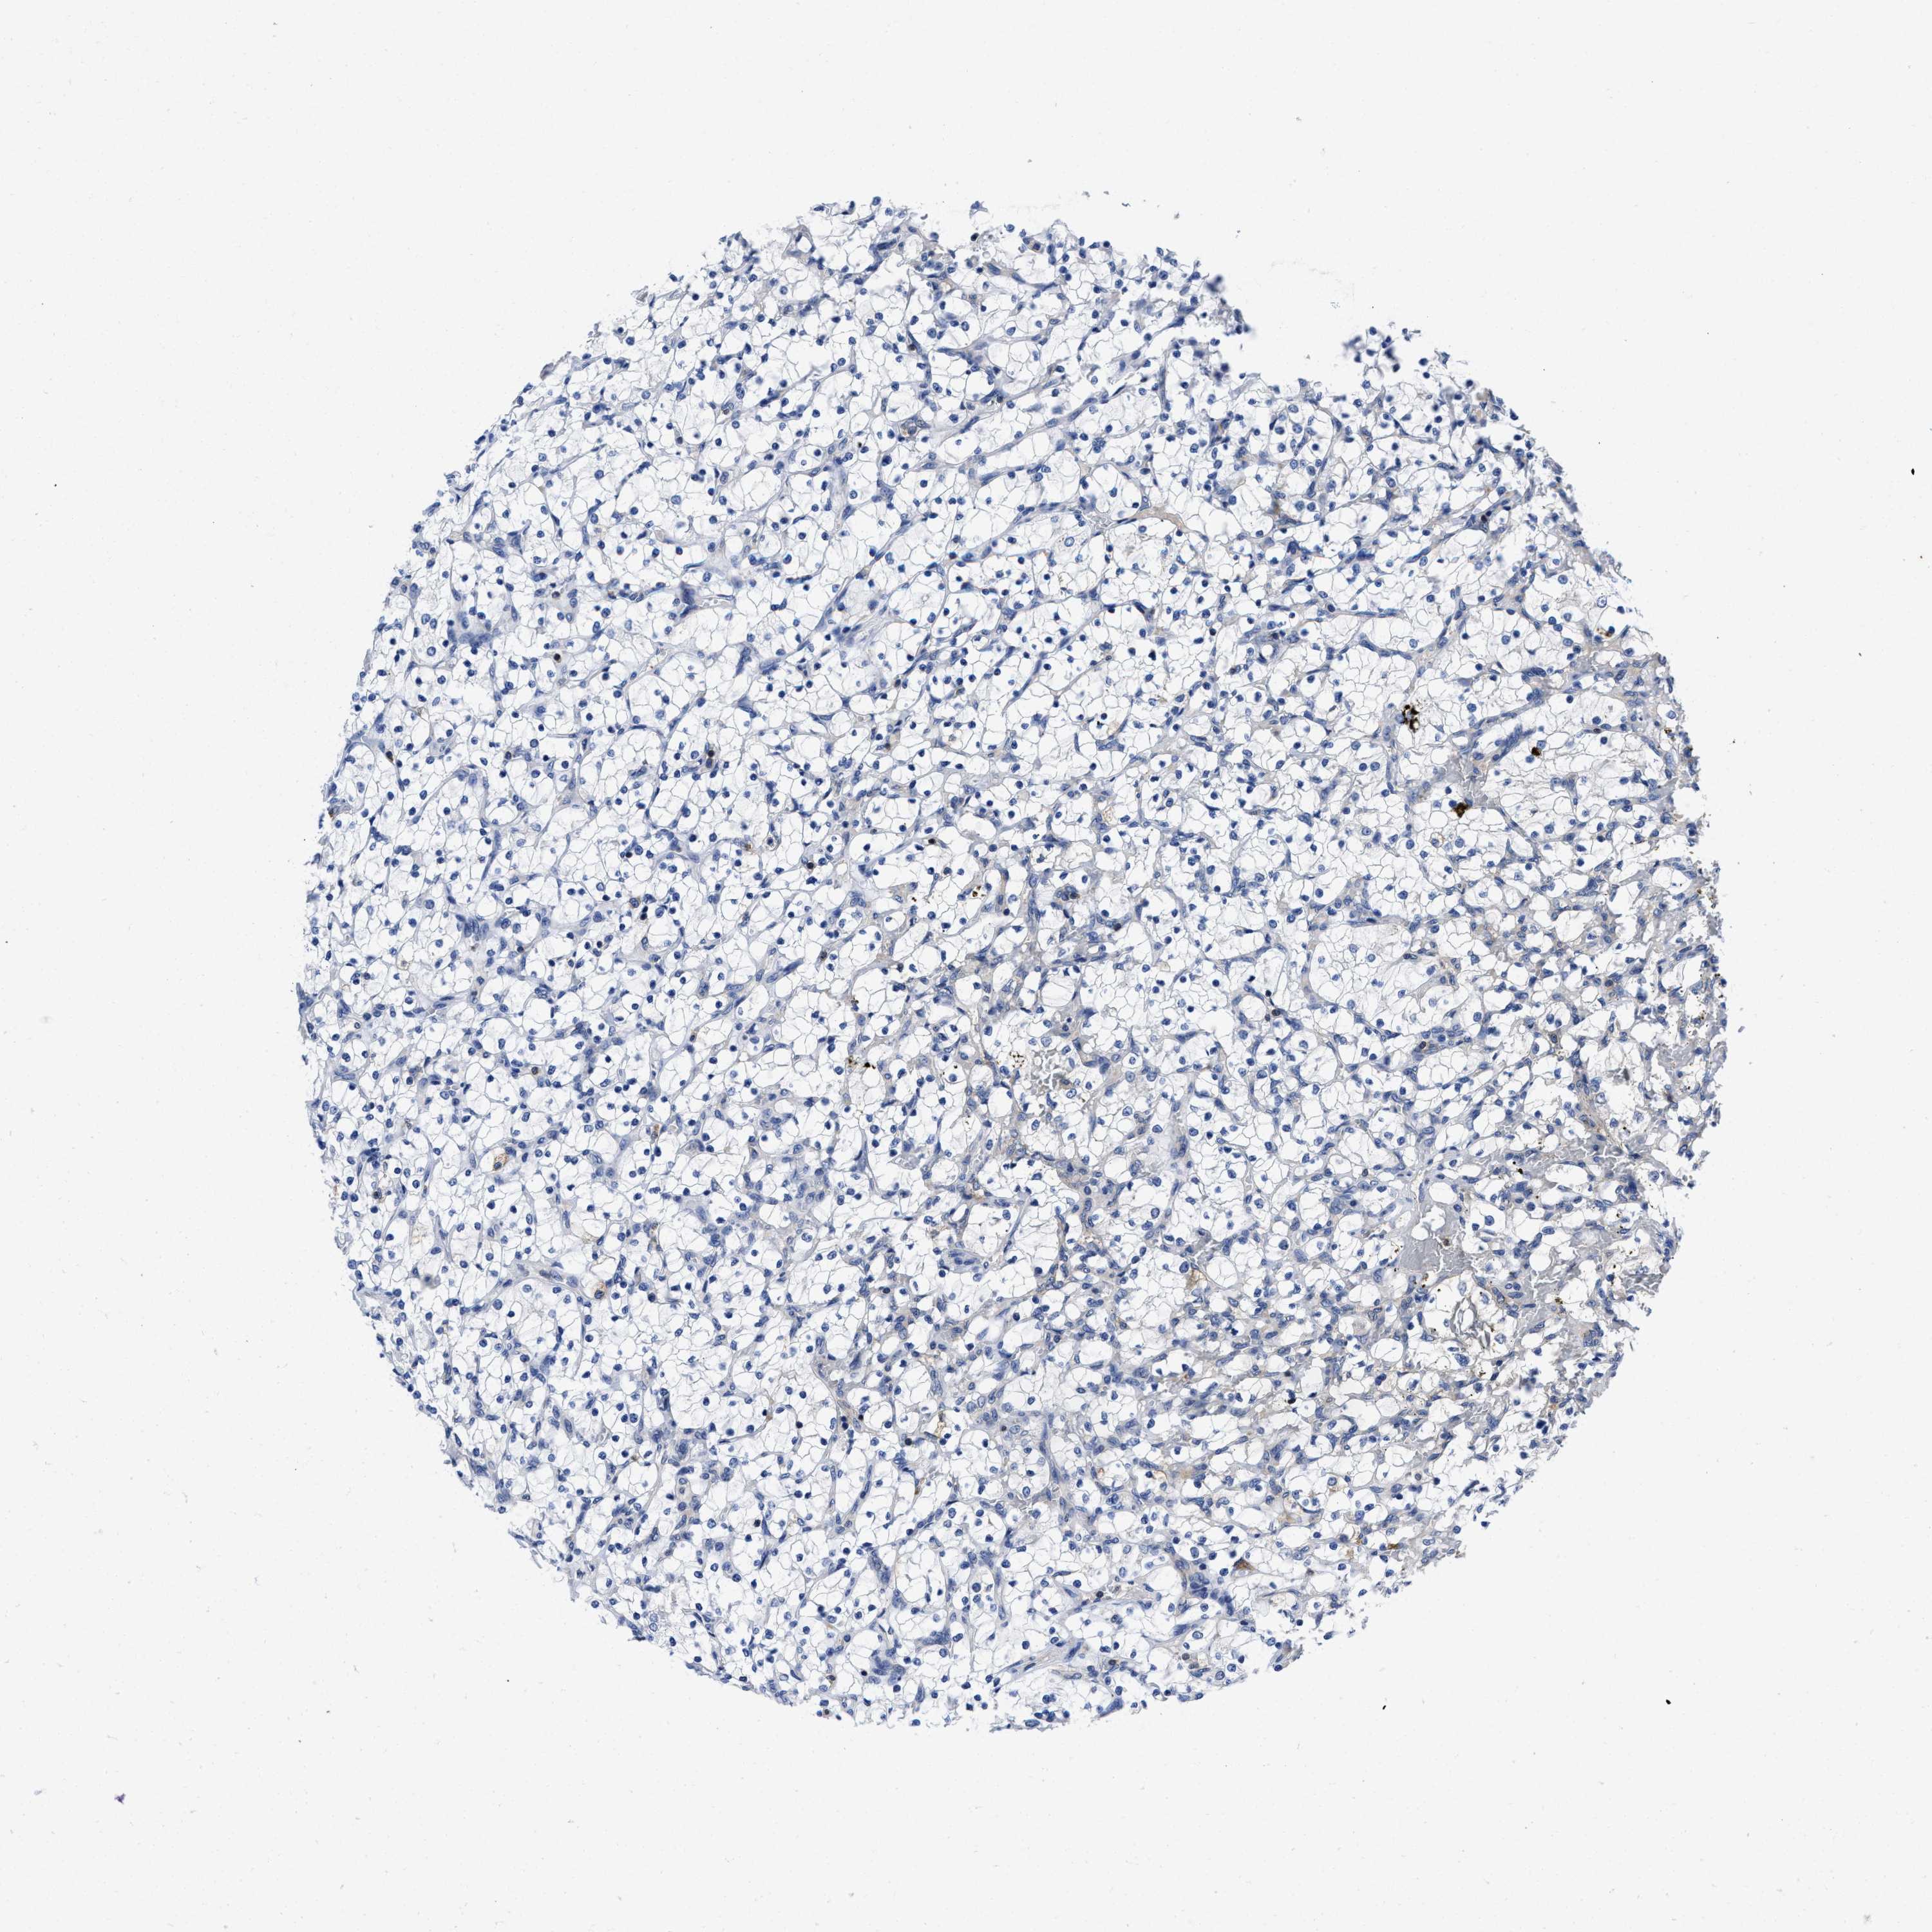

KIDNEY RENAL CLEAR CELL CARCINOMA (VALIDATION) - Interactive survival scatter ploti

The Survival Scatter plot shows the clinical status (i.e. dead or alive) for all individuals in the patient cohort, based on the same data that underlies the corresponding Kaplan-Meier plots. Patients that are alive at last time for follow-up are shown in blue and patients who have died during the study are shown in red.

The x-axis shows the expression levels (FPKM) of the investigated gene in the tumor tissue at the time of diagnosis. The y-axis shows the follow-up time after diagnosis (years). Both axes are complimented with kernel density curves demonstrating the data density over the axes. The top density plot shows the expression levels (FPKM) distribution among dead (red) and alive patients (blue). The right density plot shows the data density of the survived years of dead patients with high and low expression levels respectively, stratified using the cutoff indicated by the vertical dashed line through the Survival Scatter plot. This cutoff is automatically defined based on the FPKM cutoff that minimizes the p-score. The cutoff can be changed by dragging the vertical line or by entering a cutoff value in the square labeled "Current cut-off".

Under the Survival Scatter plot the p-score landscape (black curve; left axis) is shown together with dead median separation (red curve; right axis). Dead median separation is the difference in median mRNA expression between patients who have died with high and low expression, respectively. It is calculated as follows: median FPKM expression of dead patients with high expression - median FPKM expression of dead patients with low expression. This is intended to aid the user in visually exploring custom cutoffs and the associated p-scores and dead median separation.

Individual patient data is displayed and can be filtered by clicking on one or more of the category buttons on the top of the page. Categories describing expression level and patient information include: high, low, alive, dead, female, male and tumor stages. The scale of the x-axis can be toggled between linear and log-scale by clicking on the "x log" button. Mouse-over function shows TCGA ID, patient information and mRNA expression (FPKM) for each patient.

& Survival analysisi

Kaplan-Meier plots summarize results from analysis of correlation between mRNA expression level and patient survival. Patients were divided based on level of expression into one of the two groups "low" (under cut off) or "high" (over cut off). X-axis shows time for survival (years) and y-axis shows the probability of survival, where 1.0 corresponds to 100 percent.

YARS1 is not prognostic in Kidney Renal Clear Cell Carcinoma (validation)

Best expression cut offi

Based on the FPKM value of each gene, patients were classified into two groups and association between prognosis (survival) and gene expression (FPKM) was examined. The best expression cut-off refers the FPKM value that yields maximal difference with regard to survival between the two groups at the lowest log-rank P-value. Best expression cut-off was selected based on survival analysis .

When clicking on this number, the vertical dashed line indicating cut-off, the interactive survival plot, and the Kaplan-Meier curve will be adjusted to show results based on the best expression cut-off.

: 42.24

P scorei

Log-rank P value for Kaplan-Meier plot showing results from analysis of correlation between mRNA expression level and patient survival.

N/A

TCGA RNA samplesi

RNA-seq data is reported as average FPKM (number Fragments Per Kilobase of exon per Million reads), generated by the The Cancer Genome Atlas (TCGA) .

Normal distribution across the dataset is visualized with box plots, shown as median and 25th and 75th percentiles. Points are displayed as outliers if they are above or below 1.5 times the interquartile range. FPKM values of the individual samples are presented next to the box plot.

Average pTPM 36.0

Number of samples 100